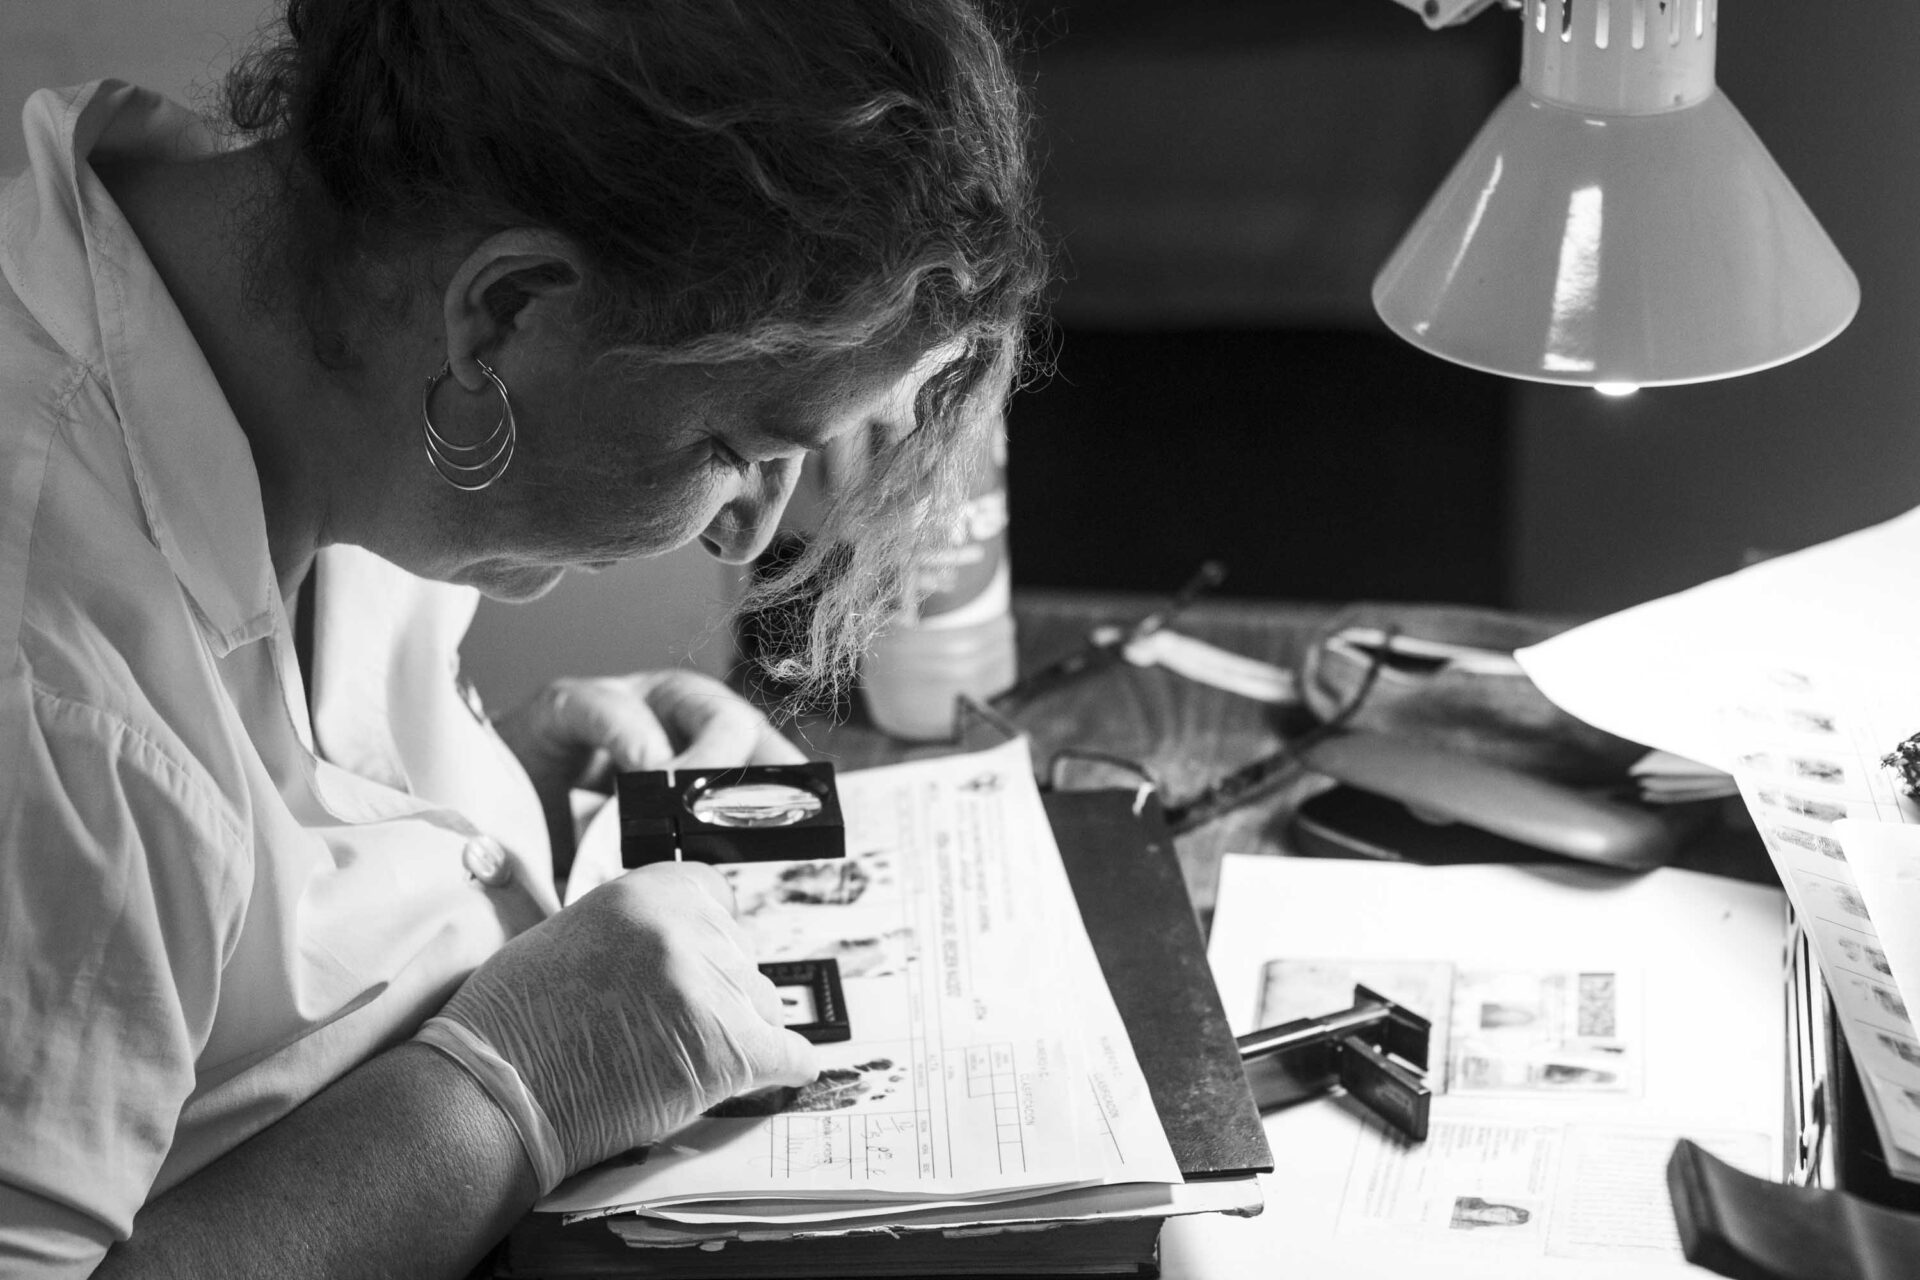

In the city of Añatuya -Santiago del Estero Province- in the north of the Argentine Republic, the Zonal Hospital maternity attends an average of 1000 deliveries per year. The prevalence of Chagas disease in pregnant women is considered one of the highest in the country because at the time of giving birth most of them present with less than 5 check-ups during pregnancy. 1 in 3 pregnant women have Chagas.

Associated with extreme and endemic poverty in 21 Latin American countries, it affects approximately 8 million people in the world, of which 1.2 million are women of childbearing age. According to the WHO (World Health Organization), more than 95% of them are unaware of their status.

In Argentina, the data is worrisome since it is estimated that there are 1.6 million infected, 7 million people at risk of being so, and 1.300 babies born with the disease annually.